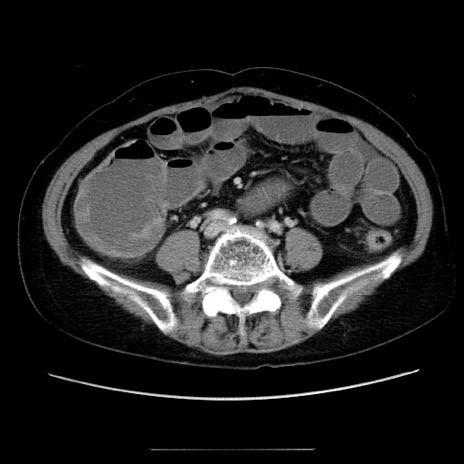

症例5(横断像)

【症例】70歳代女性

【主訴】お腹が張る

【現病歴】1週間くらい前から腹部膨満の自覚あり。昨日夜から増悪したため、本日救急外来受診。

【身体所見】意識清明、BT 36.5℃、BP 165/106mmHg、HR 80bpm、SpO2 98%、腹部:膨満、軟、自発痛・圧痛なし、触診にて不快感あり、腸蠕動音:減弱

【データ】WBC 12600、CRP 1.04